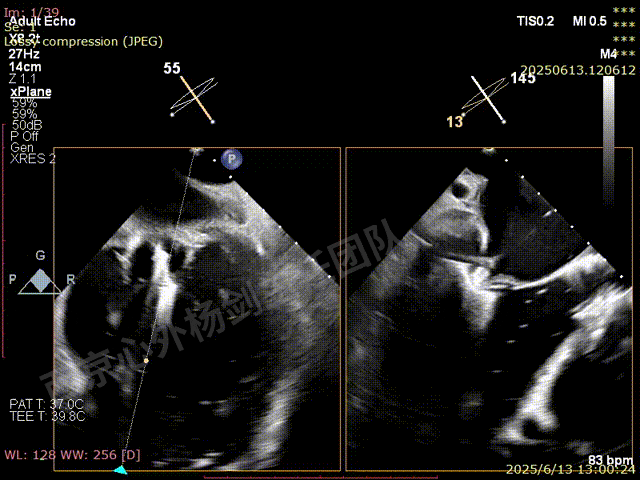

TEER术前超声评估

二尖瓣后叶栓系严重,前叶相对错位,反流束沿2区分布广泛,2偏3区处存在反流。

反流宽度至少23mm,因影像调整困难,考虑实际反流更宽。